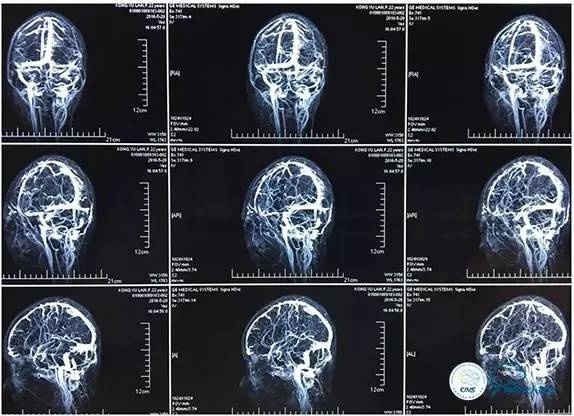

MRV

右侧ICA正位

右侧ICA侧位

右侧ICA斜位

左侧ICA正侧位

右侧VA正位

左侧VA正侧位